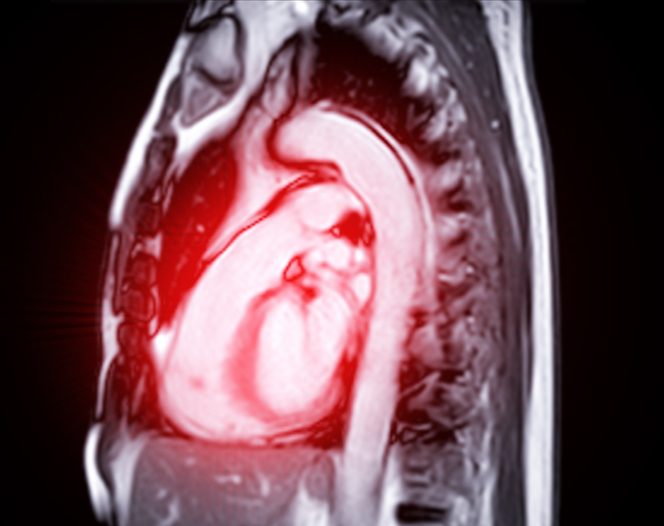

심장에는 혈액이 제 방향으로 안전하게 흐르도록 문(門) 역할을 하는 판막이 4개 있다. 이 가운데 심장의 좌심실과 대동맥 사이에 위치해, 대동맥으로 혈액이 나가는 '대문'에 해당하는 곳이 대동맥 판막이다. 대동맥 판막은 온몸으로 혈액을 내뿜기 위해 쉼 없이 열리고 닫히기 때문에 퇴행성 심장질환이 생길 수 있는 대표적인 부위다.